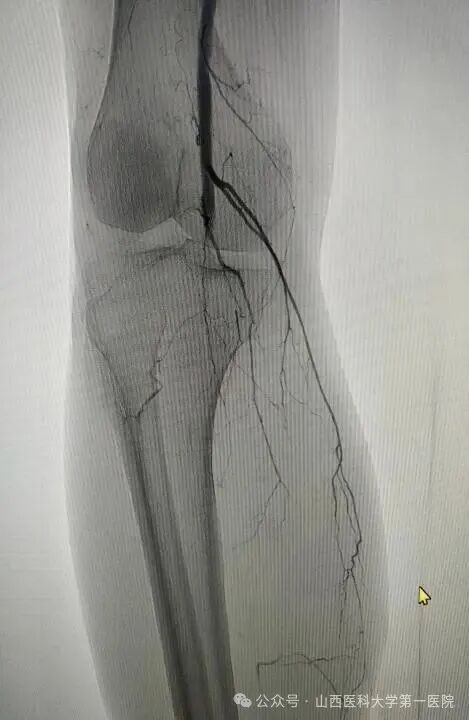

52岁王先生有长期高血压、糖尿病史,且未规范治疗控制,长期吸烟饮酒,饮酒量每日1斤左右,近年来逐渐出现间歇性跛行症状。10月20日凌晨,王先生突发右下肢发冷疼痛,当地医院下肢血管超声提示右侧髂动脉、股总动脉、腘动脉闭塞,紧急转诊至山医大一院血管外科。入院时患者右足发绀、皮温差,右足运动感觉明显减退,患侧股动脉、腘动脉、胫后动脉、足背动脉均无法触及搏动,这种急性髂股动脉血栓形成病情十分危急,死亡率40%以上,随时面临截肢与生命危险。

患者的全身状况同样堪忧,心肝肾功能异常,感染指标显著升高,“必须立刻打通血管,同时兼顾全身多器官的保护,既要保命,更要尽最大努力保肢,守护患者的生活尊严。”王贵明主任第一时间带领团队制定救治方案。为患者紧急实施了右髂动脉覆膜支架植入、球囊扩张成形及机械血栓清除等手术,成功恢复下肢血流。然而术后危机接踵而至:患者出现右小腿骨筋膜室综合征,骨科贾二龙主任医师紧急会诊后为其施行筋膜切开减压及负压封闭引流术;术后患者转入ICU,又相继出现急性肾衰竭、严重低蛋白血症、电解质紊乱、重度营养不良、发热及急性心衰等多重挑战,重症医学科与血管外科密切配合研判病情,通过抗凝、抗感染、营养支持、纠正心衰、连续性血液净化等一系列综合治疗,患者病情逐渐平稳。两周后转回普通病房,但肾功能仍未恢复。王贵明、马宏刚、刘唯棕组织全院大会诊,围绕透析管理、心功能维护、骨筋膜室综合征术后康复等制定后续方案。在肾内科、心血管内科、临床营养科等科室的共同配合下,患者全身状况日渐稳定。